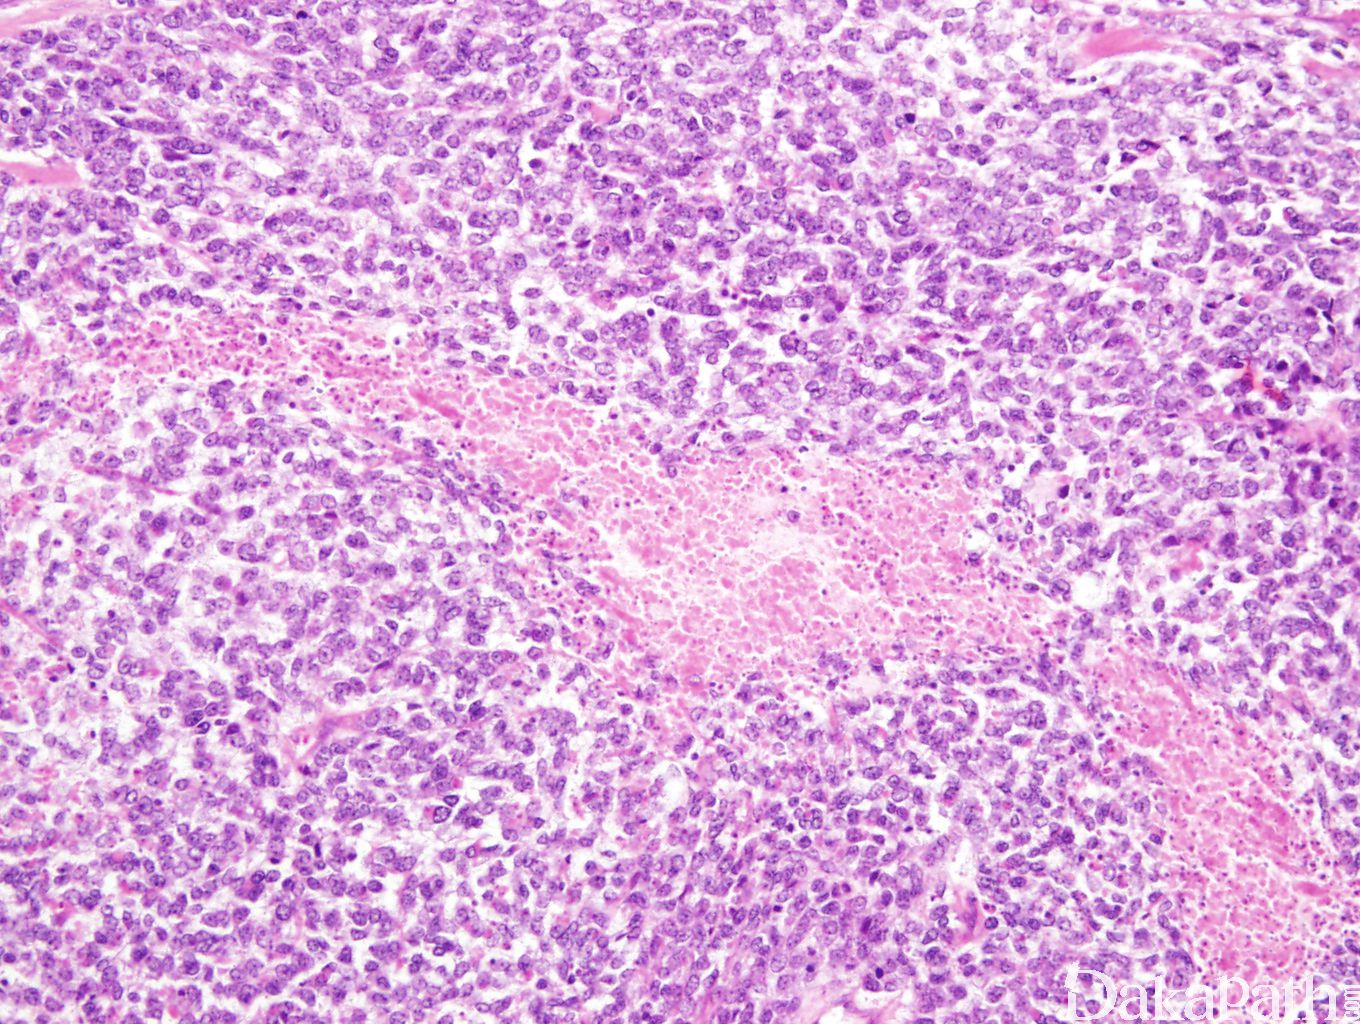

典型的肿瘤细胞呈圆形,大小一致,核 4-6 淋巴细胞大,染色质细腻,核膜不规则, 核分裂像常常 > 10/10 hpfs,非典型核分裂像也可见; 可以伴有低级别梭形细胞成分常伴黏液间质

间质可见纤细的毛细血管网间隔,类似肾脏透明细胞肉瘤

偶尔异型圆形细胞组成假乳头状/腺管状或局灶横纹肌形态,少数病例具原始神经外胚层分化,形成真或假菊型团;

常伴有坏死;